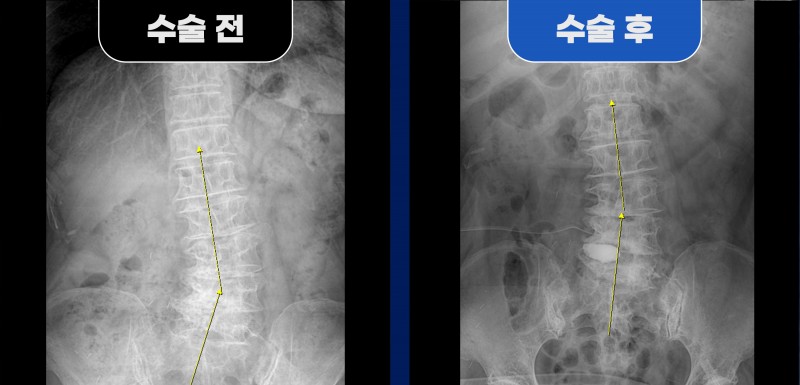

수술 후 영상 검사에서는

막혀 있던 우측 추간공이 넓게 확보된 소견이 확인되었고,

환자분은 워커를 잡고 병동 내 보행이 가능할 정도로

다리 통증이 감소한 상태로 경과 관찰 중입니다.